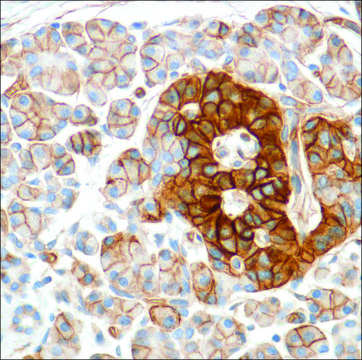

Anti-HENT1 antibody, Rabbit monoclonal

immunohistochemistry: 1:100

Human equilibrative nucleoside transporter 1 (hENT1) is a member of the equilibrative nucleoside transporter family. It is a transmembrane glycoprotein that localizes to the plasma and mitochondrial membranes and mediates the cellular uptake of nucleosides from the surrounding medium. The protein is sensitive to inhibition by nitrobenzylthioinosine (NBMPR). It is considered as a drug carrier. Nucleoside transporters such as hENT1 are required for nucleotide synthesis in cells that lack de novo nucleoside synthesis pathways, and are also necessary for the uptake of cytotoxic nucleosides used for cancer and viral chemotherapies.

Synthetic peptide derived from the internal region of human hENT1 protein.

Bruno Vincenzi et al.

British journal of cancer, 117(3), 340-346 (2017-06-24)

The expression of human equilibrative nucleoside transporter 1 (hENT1), the major gemcitabine transporter into cells, has been thoroughly investigated as a predictive marker of response to gemcitabine in pancreatic cancer and biliary tract cancers. Since gemcitabine is widely used in